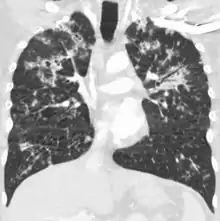

Tuberculosis of the lungs

Testing for miliary tuberculosis is conducted in a similar manner as for other forms of tuberculosis, although a number of tests must be conducted on a patient to confirm diagnosis.[4] Tests include chest x-ray, sputum culture, bronchoscopy, open lung biopsy, head CT/MRI, blood cultures, fundoscopy, and electrocardiography.[10] The tuberculosis (TB) blood test, also called an Interferon Gamma Release Assay or IGRA, is a way to diagnose latent TB. A variety of neurological complications have been noted in miliary tuberculosis patients—tuberculous meningitis and cerebral tuberculomas being the most frequent. However, a majority of patients improve following antituberculous treatment. Rarely lymphangitic spread of lung cancer could mimic miliary pattern of tuberculosis on regular chest X-ray. [15]

A case of miliary tuberculosis in an 82-year-old woman: